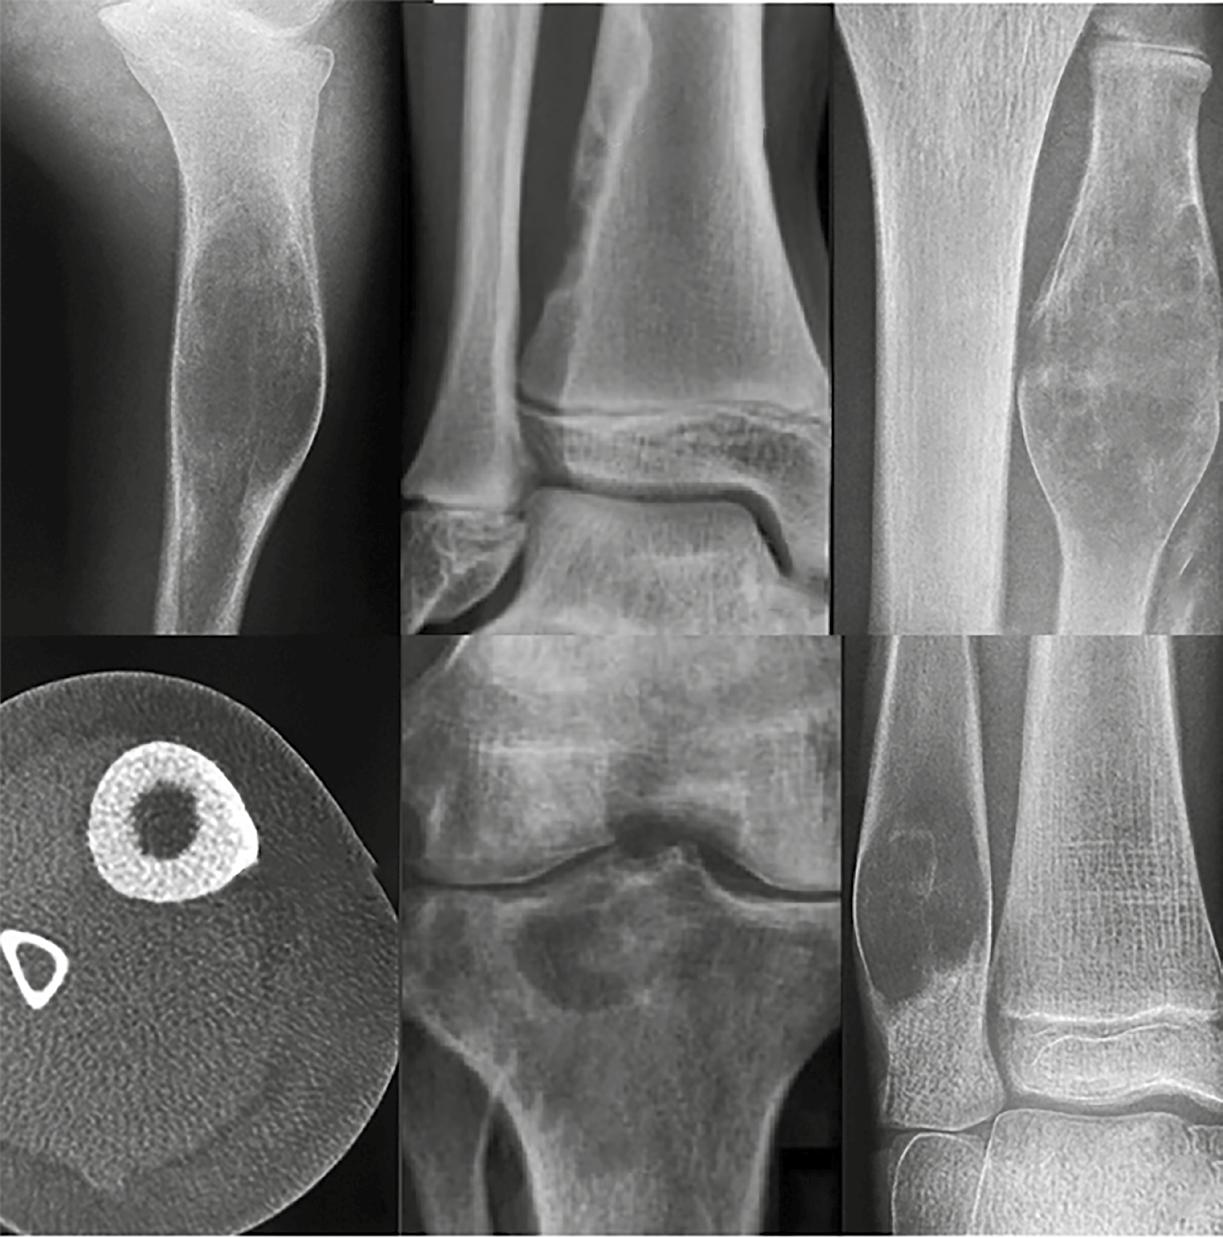

En contraste, una zona de transición amplia, mal definida y con márgenes imprecisos suele indicar un crecimiento óseo rápido y agresivo. Este patrón es característico de muchos tumores óseos malignos, como los sarcomas primarios o las metástasis en adultos mayores. No obstante, es fundamental recordar que algunas lesiones benignas también pueden presentar un comportamiento radiológico agresivo. Tal es el caso de las infecciones óseas y el granuloma eosinofílico, dos condiciones que deben incluirse en el diagnóstico diferencial de lesiones con márgenes mal definidos. A pesar de su naturaleza no neoplásica, pueden simular tumores malignos por su capacidad de destruir la cortical ósea o generar reacciones periósticas llamativas. En la Figura 3 se muestran ejemplos de estas presentaciones agresivas pero benignas.

Figura 3. Una zona de transición amplia indica malignidad o infección o granuloma eosinofílico. 1. Osteosarcoma. 2. Osteomielitis. 3. Granuloma eosinofílico. Tomada de: Jan van der Woude R, Smithuis R. Bone tumors. Differential diagnosis [Internet]. 2010 [consultado 2025 oct 13]. Disponible en: https://radiologyassistant.nl/musculoskeletal/bone-tumors/differential-diagnosis